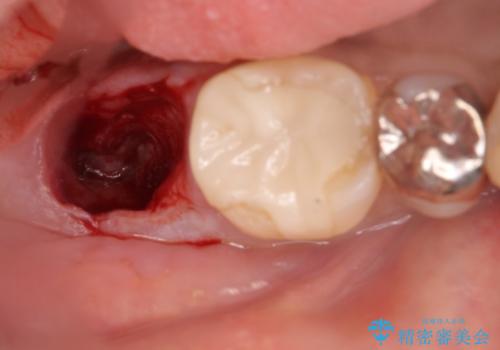

- 奥歯が痛いことを主訴に来院されました。

重度の歯周病により保存困難と診断し、抜歯後にインプラント治療を行いました。

抜歯後十分な骨の回復が認められず、単独の骨増生を行った後にインプラントを埋入しました。